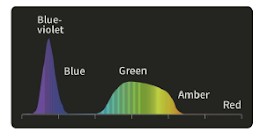

DSI: Двухцветная визуализация

Слабая проницаемость и сильное рассеивание фиолетового и зеленого света позволяет хорошо визуализировать морфологию кровеносных сосудов слизистой оболочки . Кроме того, свет в этих двух диапазонах легче всего поглощается гемоглобином, что уменьшает отражение и рассеивание и повышает контрастность между кровеносными сосудами и окружающей тканью.

Применение

- Точное обследование пораженных участков слизистой.

- Определение инфильтрации и границы пораженного участка.

- Выявление и классификация опухолевых образований.

DSI